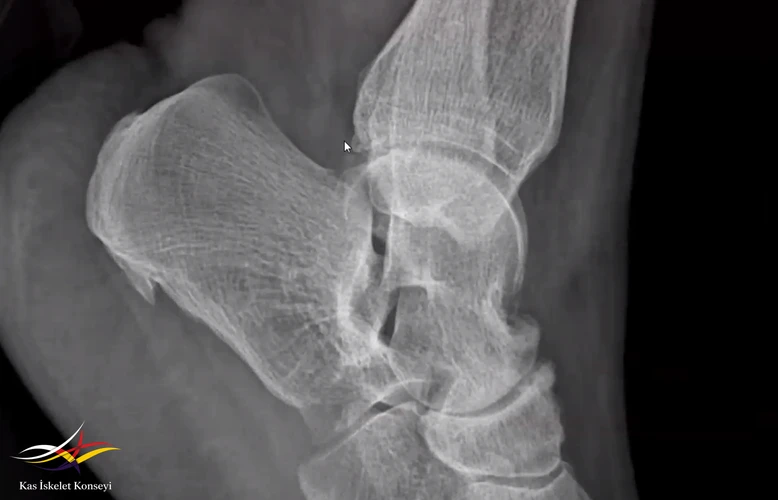

Resim 3. Ayak bileği lateral grafide kalcaneal Spur + Talonavicular eklem dejenrasyonu.

Erken yaş dejenerasyon sebepleri açısından takip ve ağrı için talonavicular eklem steroid enjeksiyonu önerildi.